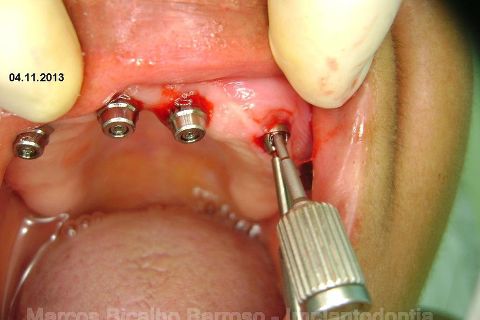

Fase Protética da Reabilitação em Maxila Atrófica

Atualização do caso clínico que já postei, "REABILITAÇÃO EM MAXILA ATRÓFICA COM IMPLANTES", um caso que inclui expansão do rebordo estreito com cinzel e martelo, expansores rosqueáveis, enxerto e instalação dos implantes distais inclinados tangenciando seio maxilar. Inclui esvaziamento do forame nasopalatino e preenchimento com biomaterial para instalação de dois implantes próximos dele. Cirurgia realizada em única sessão, com instalação dos 6 implantes. Para os colegas que não conheceram e/ou esqueceram da apresentação, este é o resumo do caso na fase cirúrgica.http://www.youtube.com/watch?v=BtvexFexRPA&hd=1

FASE PROTÉTICA DA REABILITAÇÃO EM MAXILA ATRÓFICA...incluindo a reabertura, instalação dos minipilares e PTR provisória reembasada sobre os cilindros de proteção.

Fotos do caso